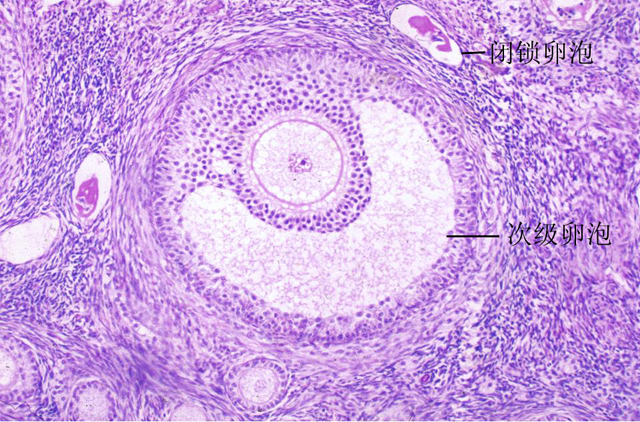

卵泡不破裂的原因

2、卵巢局部存在排卵障碍:主要是指盆腔炎症、内异症和多囊的情况。

3、一些酶的缺乏:比如卵巢内的纤维蛋白溶解酶原和蛋白溶解酶活性降低,卵泡液容易凝集,从而就不容易发生破裂。